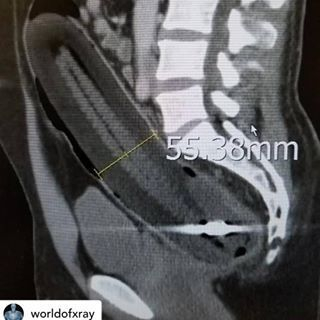

据统计,在急诊室中,男性“失物招领”的情况是女性的40倍,大部分失物是在肠道中被发现的,而且花样繁多……